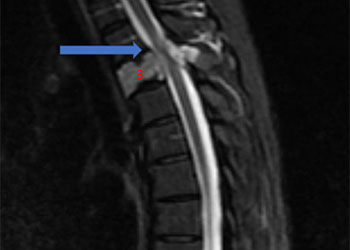

Central Cord Syndrome

Author: Yusef Imani M.D., F.A.A.N.S., Read More!